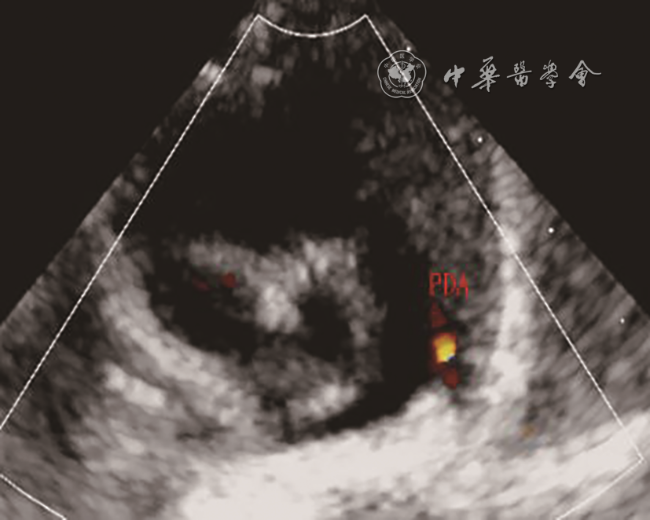

新生儿,足月顺产,Apgar评分9分;产前羊水穿刺正常。2019年10月在成都市第五人民医院分娩后发现左手掌指端紫绀;体格检查:心肺听诊胸骨左缘第二肋间疑似连续性杂音;床旁心脏超声:右位主动脉弓,左位动脉导管未闭,大动脉水平右向左分流。出生后第4天,左手掌紫绀消失。复查心脏超声:心脏房室大小正常,房室连接、心室大动脉连接关系正常;主动脉弓位于气管右侧,弓上可见3个分支,依次为左颈总动脉、右颈总动脉、右锁骨下动脉(图1);左肺动脉起始部可见宽约0.4 cm管型动脉导管未闭,彩色多普勒显示导管内左向右分流(图2);追踪导管走行,导管与左锁骨下动脉延续(动态图1);左锁骨下动脉与主动脉弓无连接关系。进一步行颈部血管超声检查左侧椎动脉,可见椎动脉血流反向(图3)。超声诊断:右位主动脉弓,孤立性左锁骨下动脉,动脉导管未闭,先天性左锁骨下动脉窃血,先天性肺动脉窃血。患儿一般情况良好,于出生后第7天出院,嘱其3个月后复查心脏超声。

图2 孤立性左锁骨下动脉患儿出生后第4天超声心动图胸骨旁大动脉短轴切面显示左肺动脉起始部见动脉导管未闭,左向右分流

注:PDA为动脉导管

Leutmer等8文献回顾表明,超过半数(59%)的孤立性左锁骨下动脉伴发紫绀型先天性心脏病,其中以法洛四联症(tetralogy of Fallot,TOF)最常见。CT和数字减影血管造影(digital subtraction angiography,DSA)可以很好显示左锁骨下动脉起源以及与主动脉弓的关系,是诊断ILSA的金标准9, 10, 11。本例患儿CTA显示左锁骨下动脉起始端线状变细并靠近左肺动脉,左肺动脉起始部发出鸟嘴样动脉导管残端是孤立性左锁骨下动脉特征性改变。超声心动图可以比较准确地诊断心内结构畸形,但对于不伴心内结构畸形的ILSA超声诊断存在局限性。特别是动脉导管闭合后,由于纵隔遮挡及肺气干扰,很难显示左锁骨下动脉的起源;超声显示同侧椎动脉血流反向有助于提示本病。不过,通过本例患儿发现,新生儿纵隔透声性明显好于成人,使得超声可以更清晰显示主动脉弓上分支起源情况,这有助于明确本病诊断。ILSA患儿胸骨上窝主动脉弓长轴切面,可见异常排列的3个主动脉弓分支,依次为左颈总动脉、右颈总动脉、右锁骨下动脉。当合并动脉导管未闭时,在高位大动脉短轴切面,可以直接显示左锁骨下动脉通过动脉导管与左肺动脉的唯一连接关系。同时,彩色多普勒可以观察椎动脉血流方向以及左锁骨下动脉与肺动脉之间导管内血流分流方向,进一步明确是否存在锁骨下动脉窃血或肺动脉窃血。